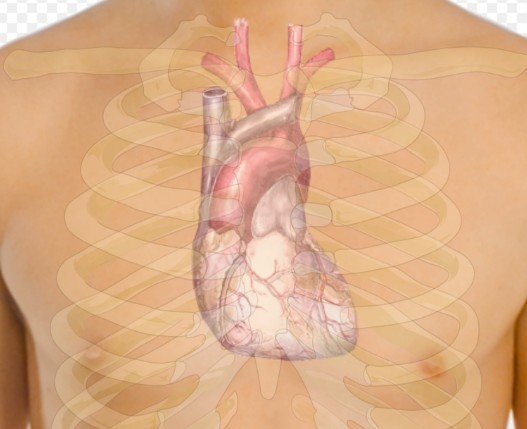

Врач рекомендует ограничивать употребление алкоголя и поддерживать режим сна, чтобы снизить риск инфаркта и инсульта. Он отметил, что зимний сезон, связанный с отпусками и праздниками, может вызвать стресс и изменения в режиме питания, увеличивая опасность сердечно-сосудистых заболеваний.

Врач предложил избегать стрессовых ситуаций, следить за качеством сна и уделять внимание здоровому питанию. Кроме того, он предупредил о возможных негативных воздействиях холодного воздуха, который может вызвать сужение кровеносных сосудов.

Ллойд-Джонс также советует пациентам, принимающим лекарства, особенно от сердечно-сосудистых заболеваний, тщательно следить за своим здоровьем и придерживаться графика приема препаратов, сообщает Газета.Ру.